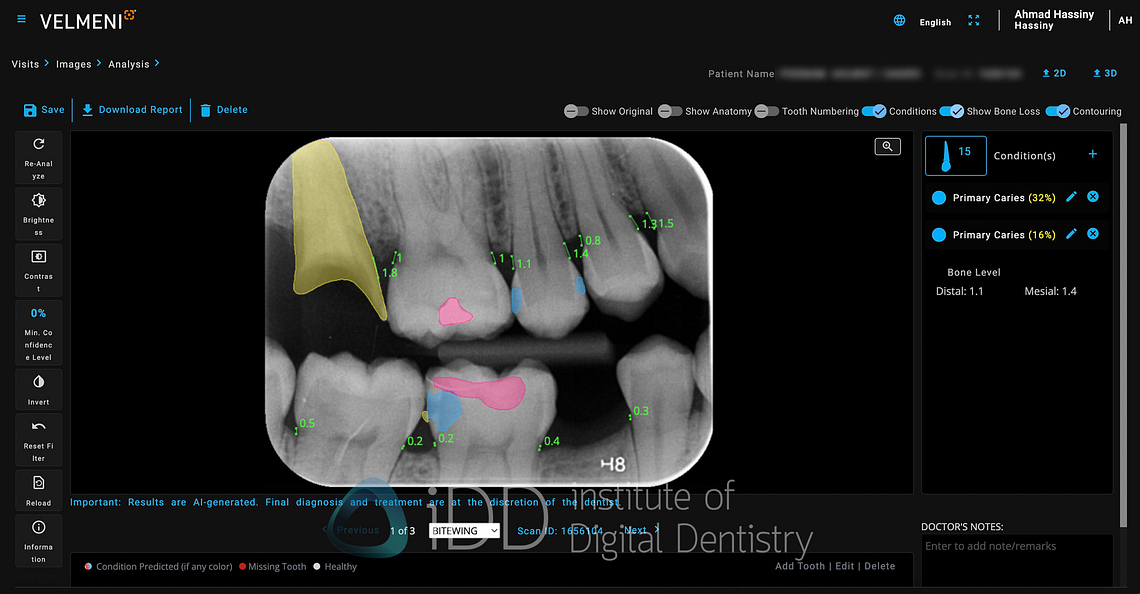

Navigation within the platform feels mostly intuitive, if somewhat utilitarian. The image viewer occupies most of the screen real estate, with AI detection controls arranged in a toolbar along the top with simple on and off toggles. A side panel includes standard image manipulation tools - brightness, contrast, and zoom controls etc.

The software automatically segments each x-ray into tooth numbers. Each type of detection (caries, bone loss, etc.) can be toggled individually by hovering over it, preventing the screen from becoming cluttered with markings. There is also a colour-coded summary at the bottom that indicates what detection has been found for each tooth.

When you click on any tooth, the window on the right provides additional details about the finding, including measurement data and confidence levels. The ability to edit or dismiss AI findings is straightforward, acknowledging that professional judgment should always take precedence over automated detections.

One of Second Dentist's useful features is its ability to toggle between different visualization styles for AI findings. The platform offers two display modes: contour shading and box indicators. The contour shading option, which I find far more effective, fills in detected areas with semi-transparent colors that follow the natural contours of the findings. This creates a cleaner, more intuitive visualization that makes it easier to understand the extent and shape of detected pathologies.

Second Dentist takes a straightforward approach to caries detection with a simple marking system. The platform uses a single color - blue - to highlight areas of suspected decay, whether it's primary caries in untreated teeth or secondary caries around existing restorations. The blue markers clearly stand out against the grayscale of the radiograph, drawing attention to suspicious areas that warrant closer examination.

Second Dentist's approach to bone level assessment uses a straightforward two-color system paired with automated measurements to streamline the detection of bone loss.

The platform keeps things simple with a two color-coding system: green lines indicate healthy bone levels (up to 2.5mm from CEJ), while pink lines signal potential bone loss (anything exceeding 2.0mm). This clear visual distinction makes it easy to spot areas requiring attention at a glance.

Second Dentist uses yellow indicators to highlight areas where radiographic calculus is detected. The AI analyzes radiographs for the characteristic appearance of calculus - those radiopaque deposits along root surfaces - and marks them for easy identification.

Second Dentist uses a two-color system for marking existing dental restorations on radiographs. Fixed prosthetics like crowns and bridges are highlighted in yellow, while direct restorations such as composite or amalgam fillings are marked in pink.